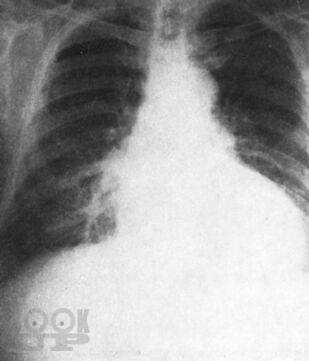

Монография всемирно известного автора посвящена вопросам клинической диагностики заболеваний сердца. Детально освещены общее исследование больного, сбор анамнеза и анализ жалоб, оценка симптомов, полученных при физикальном обследовании, а также при использовании рентгенологического и электрокардиографического методов. Для каждого заболевания автор выделяет решающие симптомы-“ключи”, помогающие установить точный диагноз.